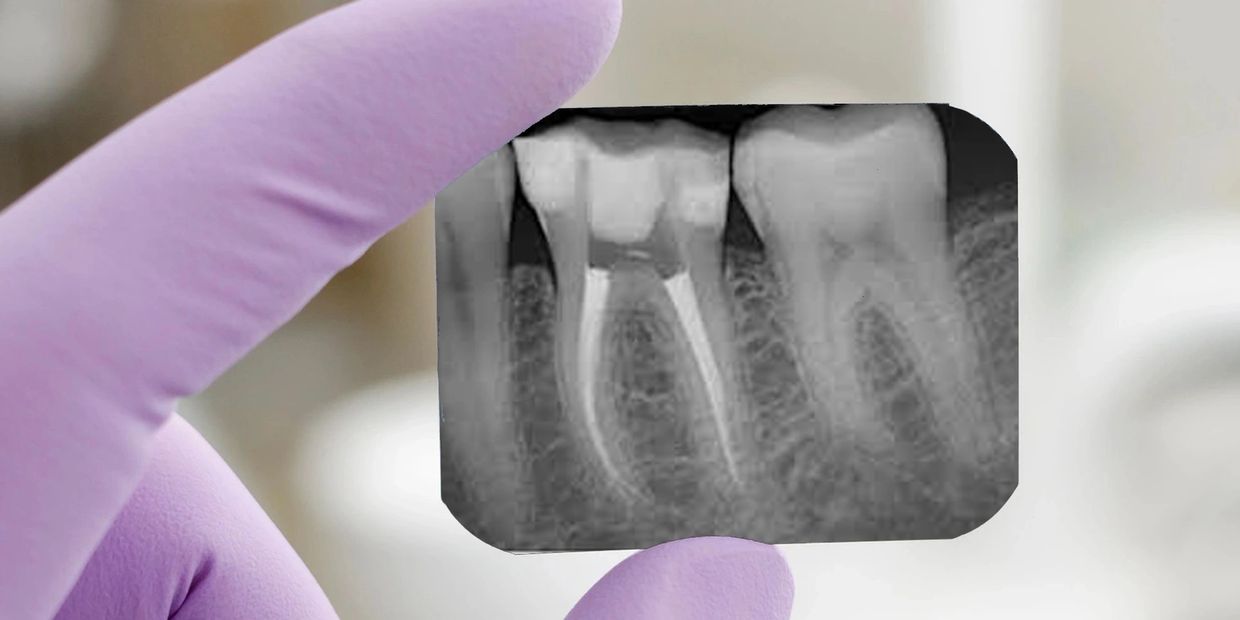

The root canal usually takes one to three visits. First, you have dental X-rays to check the extent of damage.Before having root canal treatment, your dentist may take a series of X-rays of the affected tooth. This allows them to build up a clear picture of the root canal and assess the extent of any damage.

you can see here before and after treatment.Your front incisor and canine teeth (biting teeth) usually have a single root containing one root canal.

The premolars and back molar teeth (chewing teeth) have two or three roots, each containing either one or two root canals. The more roots a tooth has, the longer the treatment will take to complete.

Immediate computersied on chair process of taking x-rays. Good bye to washing films, dark rooms and wait for the results.

Determines the exact length of invisible roots.